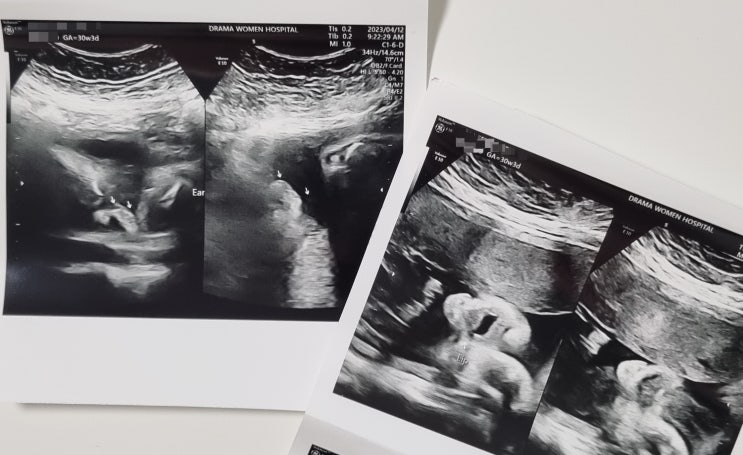

[임신일기] 30주 3일, 2차 정밀초음파, 좋은날에드라마여성병원

30주 3일 이야기 안녕하세요 양이입니다 : D 지난 번 임당검사 포스팅을 했었는데 벌써 한달이 지나 2차 ...